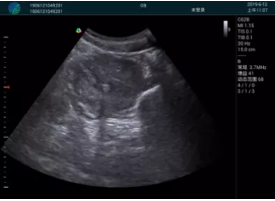

抽吸結(jié)束后縱切子宮,孕囊已被完全抽吸,未見明顯殘留

橫切子宮,發(fā)現(xiàn)右側(cè)宮腔靠近宮角處有少許脫模樣殘留

M20引導(dǎo)下,抽吸針找到右側(cè)宮角處再次清掃

二次抽吸后再次進(jìn)行超聲檢查,宮腔未見殘留,宮腔線清晰顯示